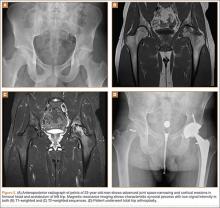

Comparisons between the synovectomy-only and synovectomy-with-arthroplasty groups are listed in Table 2. Synovectomy patients were younger on average than arthroplasty patients, but the difference was not statistically significant (P = .28). Only 6 studies distinguished between local and diffuse PVNS histology, and the diffuse type was detected in 87.0%, with insufficient data to detect a difference between the synovectomy and arthroplasty groups. In studies with documented radiographic findings, 75.0% of patients had evidence of joint space narrowing, which was significantly (P = .03) more common in the arthroplasty group (96.7% vs 31.3%).